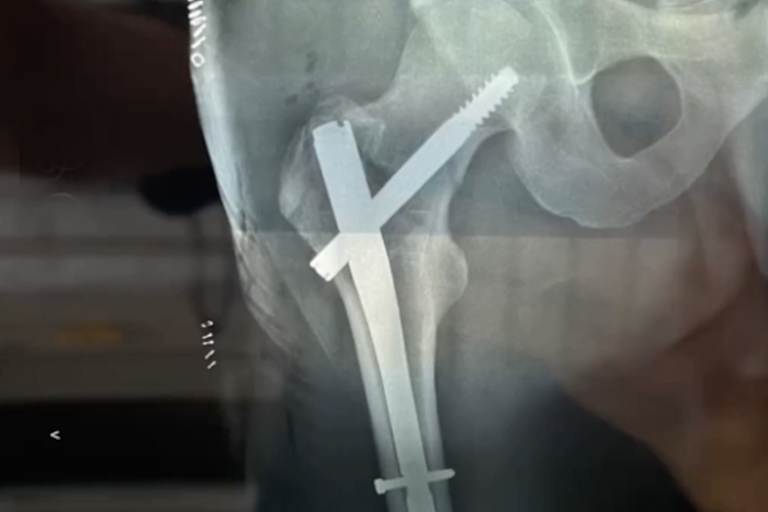

Auf den Röntgenbildern ist eine Hüftluxation und ein Oberschenkelhalsbruch zu erkennen, deren Bruchstücke mit Nägeln und Schrauben fixiert wurden. Damit wird der Berliner mehrere Monate ausfallen. Haase verletzte sich schon Anfang des Jahres unmittelbar nach dem Auftakt der US-Supercrossmeisterschaften der 450er Klasse in Anaheim (Kalifornien). Mit gebrochenem Fuß während des Trainings für das Rennen in Oakland musste er seine US-Mission nach nur einem Wettkampf abbrechen. In Anaheim konnte er sich auf Anhieb direkt fürs Abendprogramm qualifizieren. Im Juni tauchte Haase dann am legendären Teterower Bergring auf, den er nach eigenem Bekunden nur vom Hörensagen kannte. Getreu dem Motto, "er kam, sah und siegte", gewann Haase auf der extrem schnellen Grasbahnstrecke, die schon so einigen bekannten Motocrossern das Fürchten lehrte, sämtliche Punktläufe sowie das Finale um den Teterower Hechtjungenpokal. Außerdem startete der Freestyler auch in der Motocross-Europameisterschaft der Zweitakter EMX2T, die er auf Rang 14 beendete. Darüber hinaus startete er erfolgreich bei Hard Enduro Rennen wie den Red Bull Romaniacs, beim Supermoto in St. Wendel und beim Flattrack in Wolfslake. Kai Haase fährt auf allem, was zwei Räder hat. Und er beherrscht den Frontflip Bonk, der ihn weltbekannt gemacht hat.